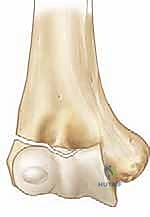

Articular Reduction and Provisional Fixation

Once the anterior aspect of the fracture is exposed, the joint must be thoroughly irrigated to evacuate the fracture hematoma. Small curettes or a dental pick are utilized to meticulously remove any interposed periosteum, organized clot, or small osteochondral debris that would block an anatomical reduction. Visualization of the articular surface is paramount; the surgeon must see the cartilage of the capitellum and the trochlea to ensure perfect congruity.

Reduction is achieved by manipulating the fragment using a combination of direct pressure and positioning of the arm. Often, supinating the forearm and applying a gentle varus stress can help unlock the fragment. A sharp dental pick or a small bone tenaculum can be used to carefully manipulate the metaphyseal portion of the fragment. The reduction is judged visually by assessing the articular cartilage anteriorly and the metaphyseal fracture line laterally.

Once anatomical reduction is visually confirmed, it is provisionally held in place. This can be done with a smooth K-wire used as a "joystick," or by having an assistant maintain pressure with a dental pick. The reduction is then rigorously verified under multi-planar fluoroscopy. The surgeon must scrutinize the AP, lateral, and oblique views to ensure there is no residual step-off, gap, or rotational malalignment.

Definitive fixation is standardly achieved utilizing two or three smooth Kirschner wires (K-wires), typically 1.6 mm or 2.0 mm in diameter, depending on the size of the child. The trajectory of these wires is critical for biomechanical stability. The first wire is usually driven from the lateral epicondyle, directing it proximally and medially, aiming to engage the intact medial cortex of the distal humeral metaphysis.

The second wire should be placed divergently from the first to maximize rotational stability. A common and highly effective configuration is to place the second wire slightly more anteriorly and direct it more transversely across the distal humerus, aiming for the medial column above the olecranon fossa. It is imperative to avoid penetrating the olecranon fossa with the K-wires, as this will mechanically block elbow extension.

Clinical & Radiographic Imaging Archive